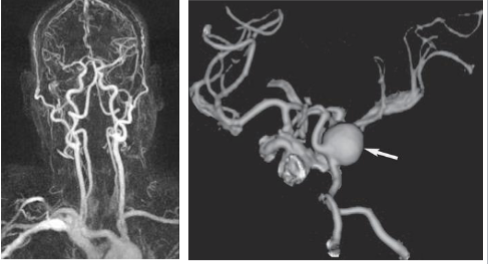

What is this and what type of scan

CT angio